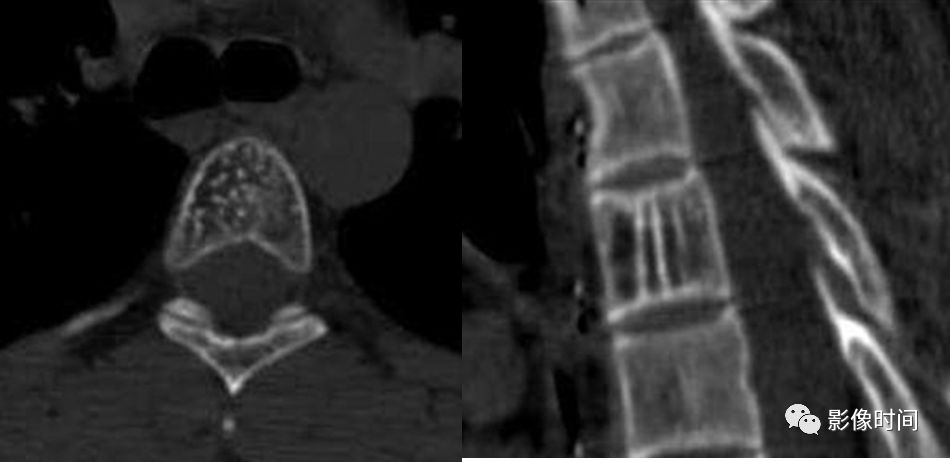

10栅栏征

栅栏征(The Palisade sign),也称灯芯绒椎体(corduroy vertebra)或灯芯绒征(corduroy sign)

脊椎椎体因病变导致骨小梁吸收、稀疏,为满足承重需要,存留的纵向骨小梁粗大;粗大骨小梁间以细条状密度减低区,形成栅栏样影像,故称栅栏征或灯芯绒椎体。

栅栏征最常见于血管瘤,以单个脊椎居多;骨质疏松如泛发性骨质增生症、老年性骨质疏松等亦可呈现此类表现,一般见于下胸椎、上部腰椎的多个椎体,只是伴有普遍的骨密度减低。有时自颈椎至腰椎全部椎体均出现栅栏征。栅栏征主要见于椎体。

病例 1,脊柱血管瘤。胸腰椎 CT 冠状位、矢状位 MPR 重建示胸 12 椎体松质骨密度降低,其中可见粗大骨小梁呈栅栏状。